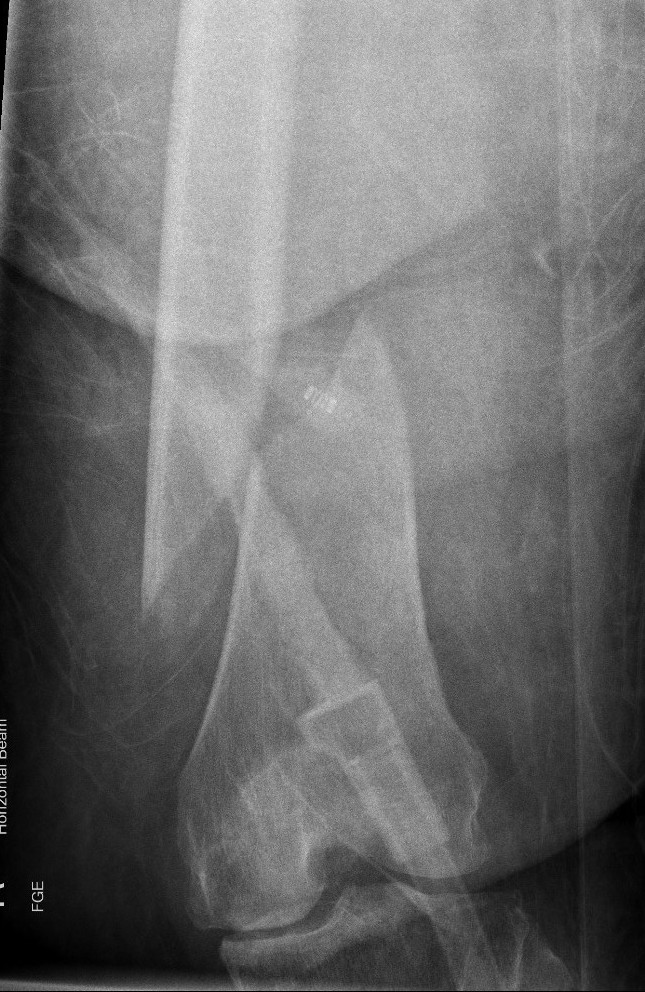

Type C: Complete articular

Xray / CT

Options

Bridging External Fixation

Indications

- compound wound

- damage control orthopedics